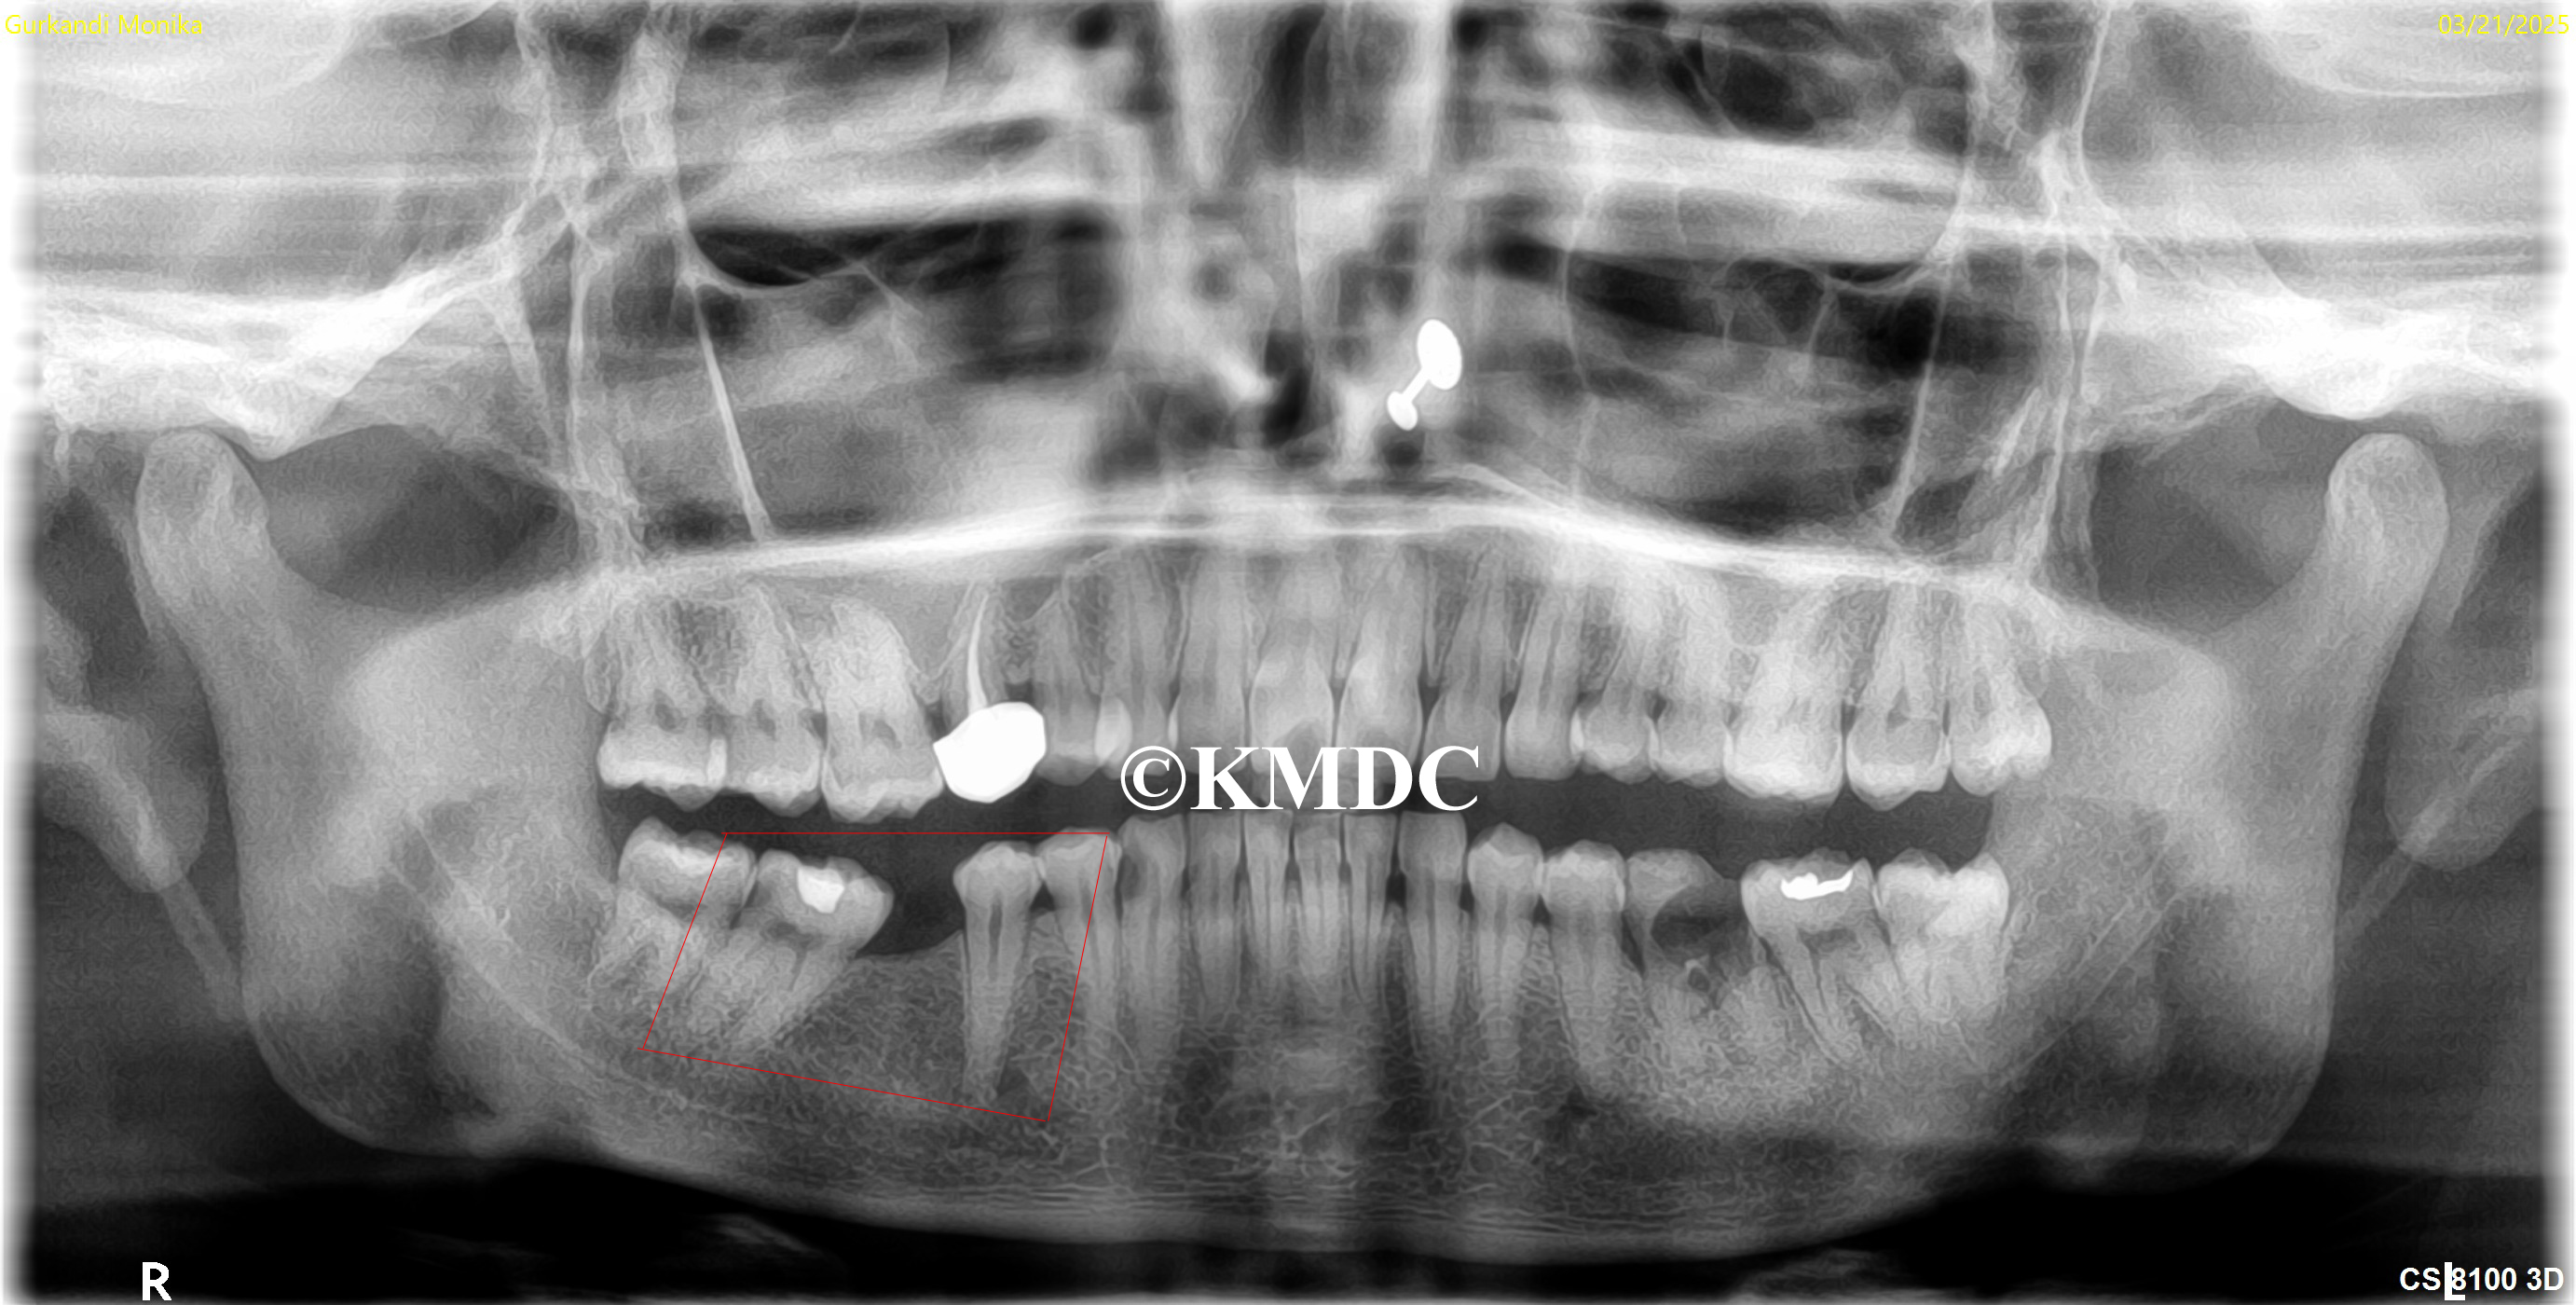

Clinical Gallery